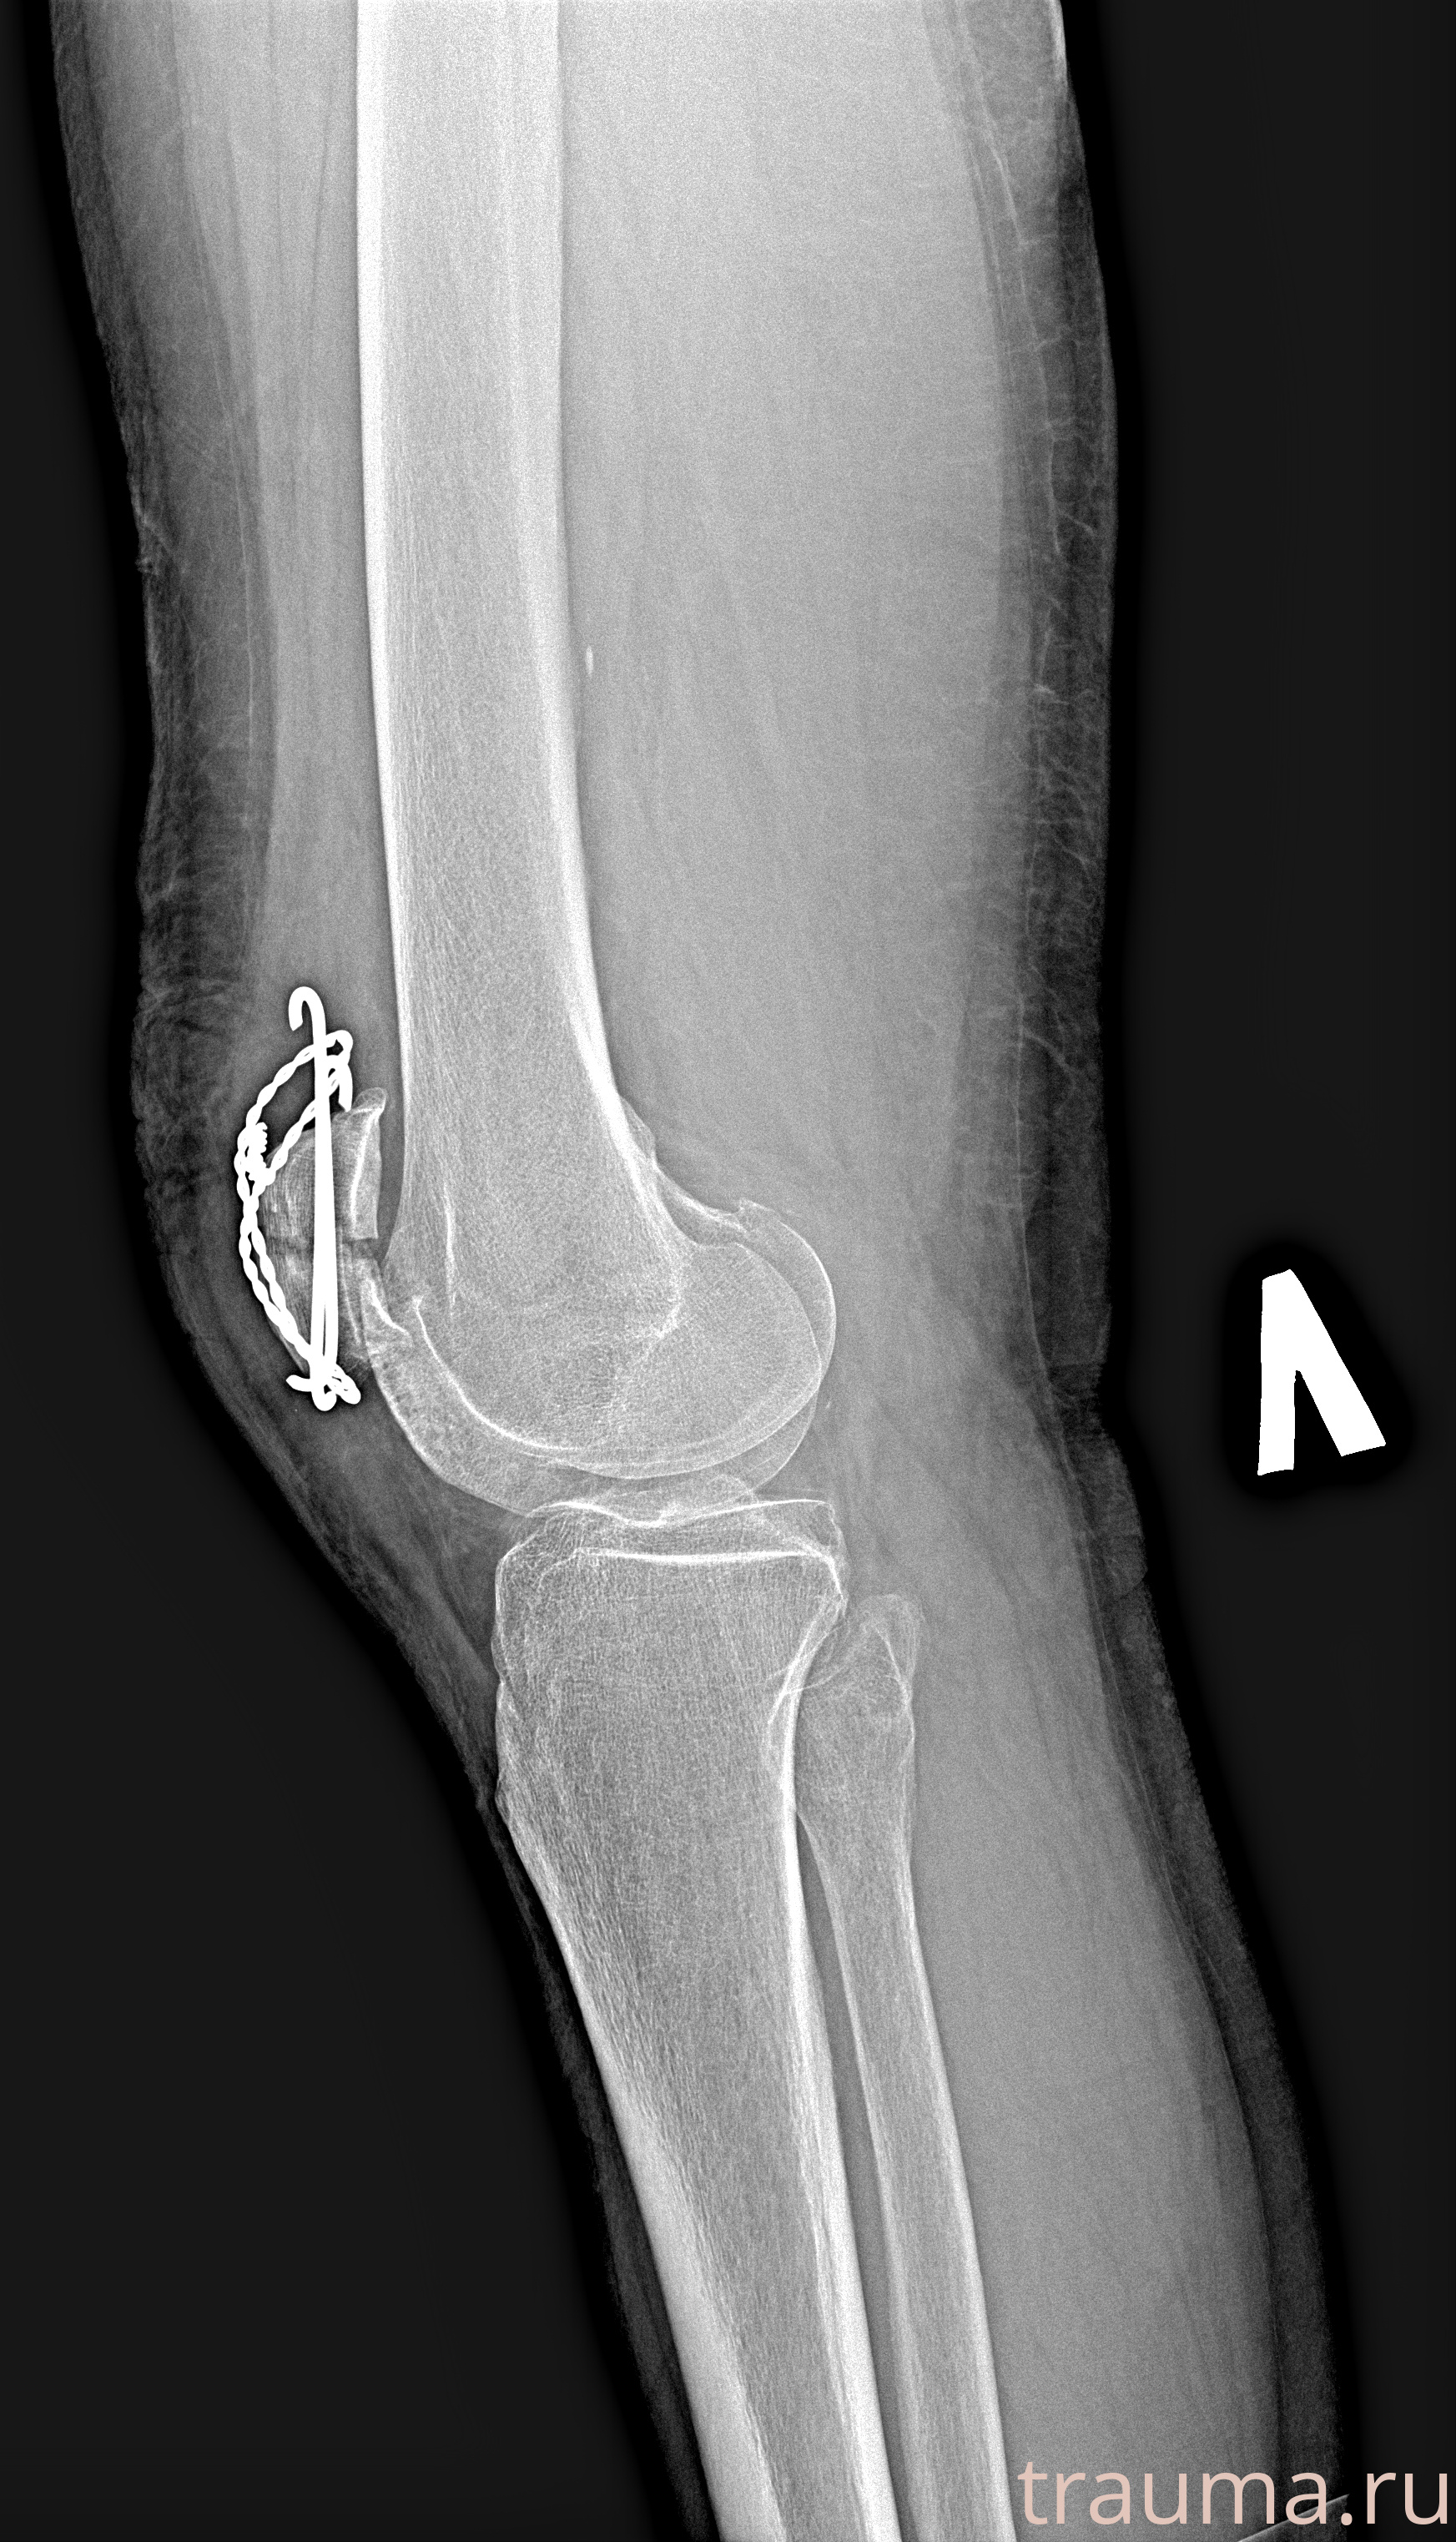

Рентгенограммы